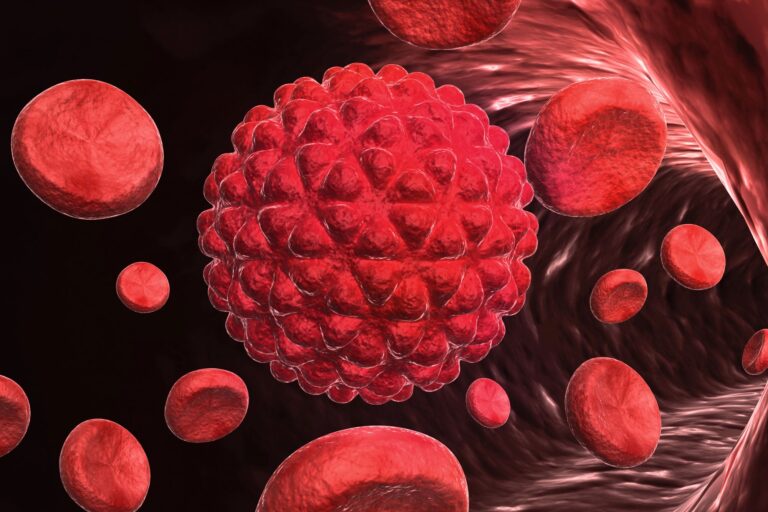

「もう治療法がない」と言われた患者に光…がんが30%小さくなった新薬の衝撃

新薬「GRWD5769」により、免疫療法が効かなかったがん患者の腫瘍が30%縮小する可能性が示された。

1人約240万円でも予約殺到…10億円超の収益を上げた国が話題 ネパール政府はエベレストの登山許可料で過去最高の10億ネパールルピーを収入し、登山者数も増加中です。 「もう治療法がない」と言われた患者に光…がんが30%小さくなった新薬の衝撃 新薬「GRWD5769」により、免疫療法が効かなかったがん患者の腫瘍が30%縮小する可能性が示された。

「もう治療法がない」と言われた患者に光…がんが30%小さくなった新薬の衝撃 新薬「GRWD5769」により、免疫療法が効かなかったがん患者の腫瘍が30%縮小する可能性が示された。 中国で紙おむつの有害物質問題が拡大…当局が合同調査に着手 中国の乳幼児用紙おむつからホルムアミドが検出されたとの疑惑を受け、当局は合同調査団を設置し、調査を開始した。